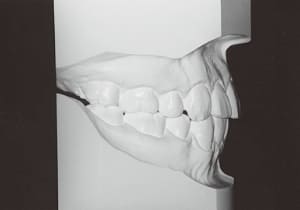

The Class II condition is pronounced, with a significant overjet of 12.5 mm(3). Although the teeth size are large, crowding is relatively mild. The maxillofacial structure has good depth and a robust bone framework(5). The mandible itself is solid , robust gonial angle, but there is significant anterior-posterior displacement relative to the maxilla(ANB 10.0°). While there is no confirmed history of thumb-sucking or similar habits, the lower lip is already pushing up against the maxillary incisors. The cause of this condition is unknown.

The first phase of treatment involved extracting the left and right maxillary deciduous canines. The space created was used to forcibly retract the four anterior teeth, thereby aiming to improve lip closure function (6–9, 11). Morphological changes suggest that lip function differed before and after treatment (6, 9). Subsequently, the first premolars erupted, but extraction is planned to secure space for canine eruption (10). A Class II molar relationship remains, but the significant overjet has improved (11).